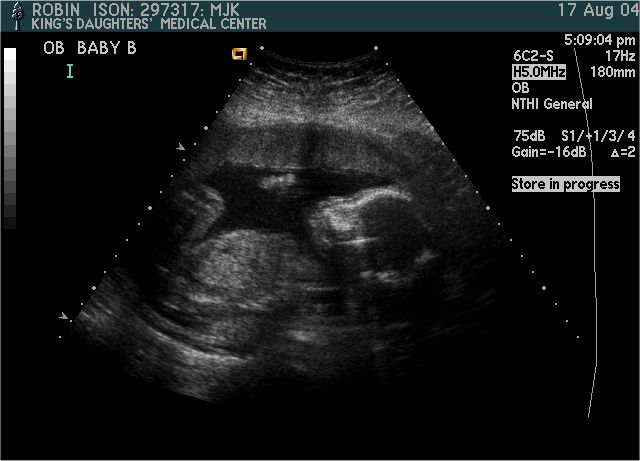

Baby B

Pictures from Ultrasound at 20 weeks.